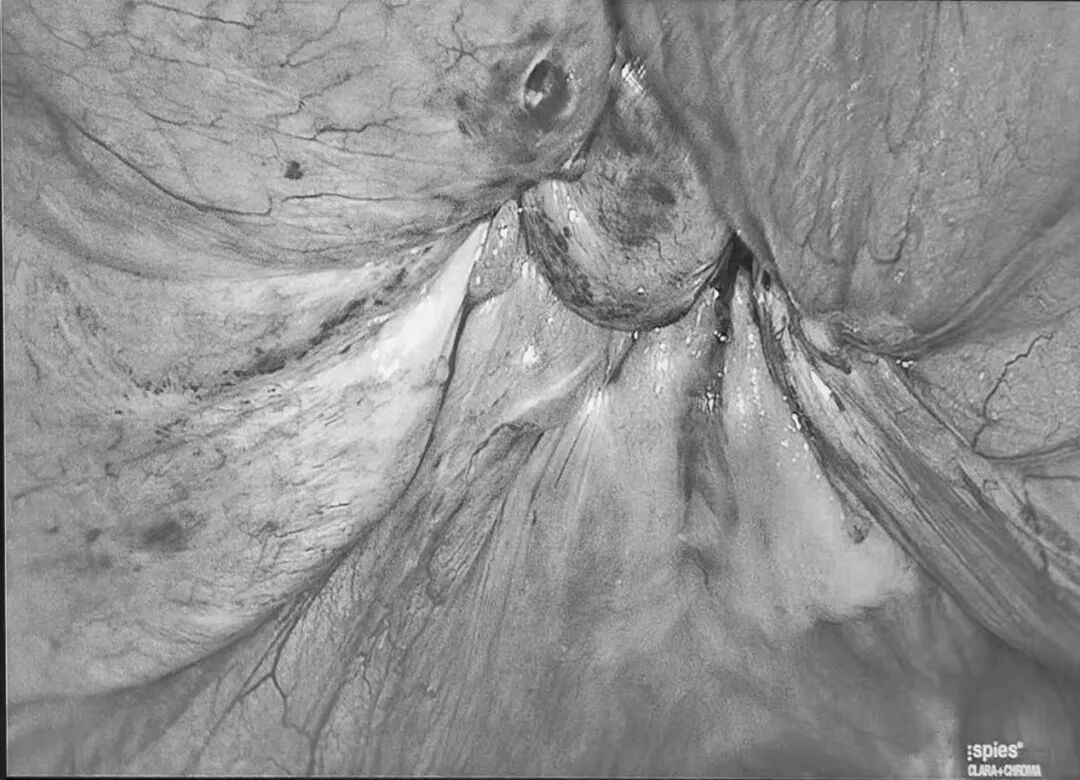

腹部CT显示:刘女士左下腹腹壁缺损直径4cm,疝囊大小8*4cm,内有腹部组织突出,诊断为腹壁疝。决定行腹腔镜下腹壁疝修补术,术中可见大网膜经腹壁缺损突出腹腔外,术中将突出腹腔的大网膜还纳回腹,用疝气钩针修补腹壁缺损后,用防粘连疝补片覆盖于缺损处,最后用疝钉固定疝补片。

▲利用疝气钩针修复后

相比于传统开刀疝修补术,新术式微创下行腹壁疝修补术,应用防黏连疝气补片,损伤小,痛苦小,恢复快,又可有效的避免疝复发的可能。术程顺利,术后未见排异反应。